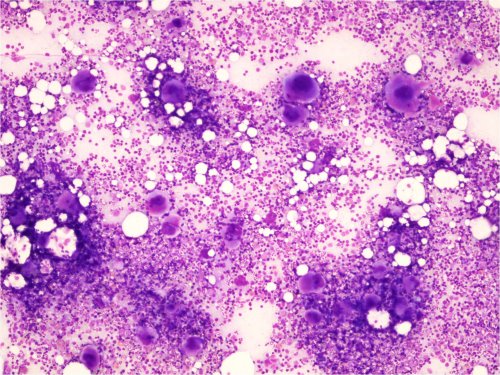

Akuutti ITP

• Yleinen lapsilla

• Perifeerisessä veressä trombosytopenia, joka joskus hyvinkin vaikea (B-Trom jopa < 5)

• Luuytimen megakaryosyyttien määrä lisääntynyt

• Megakaryosyyttien nuoruusmuotoja esiintyy, samoin pienikokoisia muotoja

• Trombopoieesin turnover lisääntynyt

• Kyseessä trombosyyttien immunologinen kato

• Muut solulinjat normaalit

Kuva 22. Akuutti ITP, luuytimen yleiskuva. 2 kk:n ikäinen vauva. Runsas megakaryosyyttien määrä yhdessä perifeerisen trombosytopenian kanssa sopii akuuttiin ITP:hen. 1) Osa megakaryosyyteistä on nuoria ja pieniä ylivilkkaan muodostuksen vuoksi.